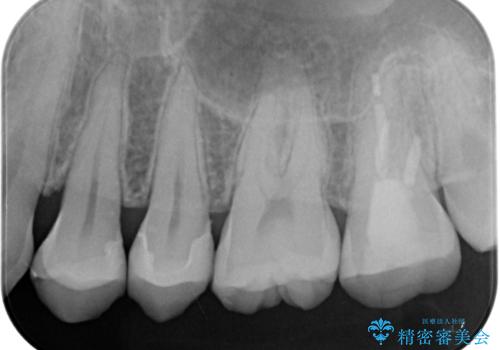

- すごく前に治療したレジンがざらつくので治療したいとのことで来院された患者様です。十年ほど前に根管治療を行っており、症状は特に何もない状態でした。根管治療を行っている歯は咬合力に対して鈍くなり破折しやすくなるため、最終的には被せものによる補綴治療を行う必要があります。

ラバーダム防湿下でコンポジットレジンを除去しファイバーコア築造を行い、オールセラミッククラウンに適した形に整えました。